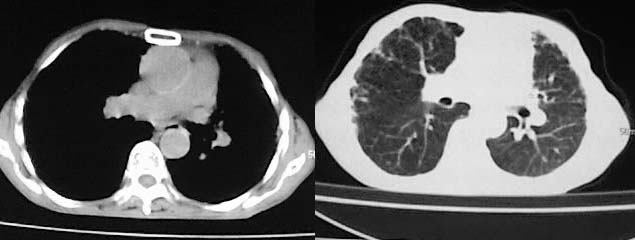

以下是引用有风的日子在2008-5-2 12:13:00的发言:[br][emb10][br][br]肺ca?有病理支持吗?[br][br]我看更象是肺tb并支扩、间质性肺炎。最好拿个病理结果来,不然这点影像资料诊断肺ca是难以服人的![br][br]至于主动脉瘤的诊断问题,国外认为≥4.0cm就可诊断了,国内对此诊断标准更为严格。患者升主动脉明显增粗,即>4cm。你诊断个升主动脉扩张并不为过!

以下是引用zjzjr在2008-5-2 14:39:00的发言:[br]支持双侧继发型肺结核,左侧胸膜肥厚,慢性支气管炎伴间质纤维化.